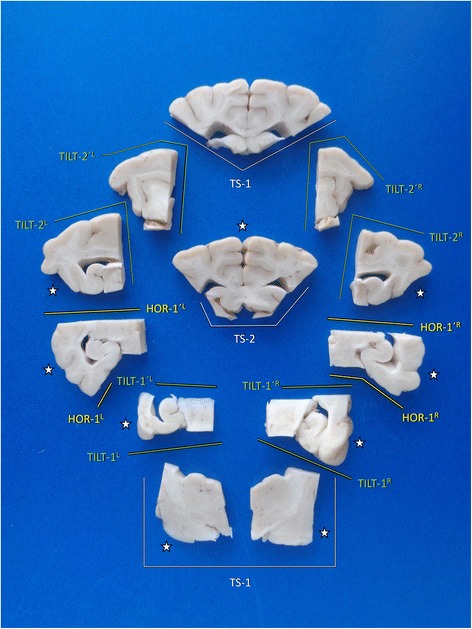

A survey on the brain slides possibly sampled by trimming of tissue block A is provided in Fig. 11.

Fig. 11.

Overview of main brain slabs of Block A in correct angle of section. A selection of these may be further processed for histology. Asterisks mark our recommendation for systematic epilepsy pathology studies